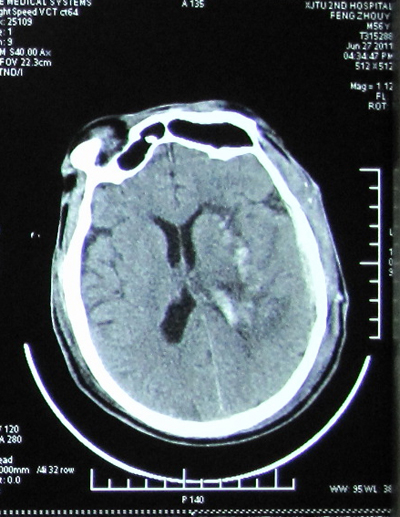

患者男性,56岁,因“突发左侧肢体活动不灵19小时,意识不清18小时” 于2011年6月23日急诊收住我科,复查颅脑CT显示“右侧基底节区及丘脑出血(量约68毫升)并破入脑室”。完善各项术前准备后,在手术麻醉科张珍妮主治医师、薛鹏军以及我科宋琴的协助下,吕健副主任医师主刀、宋千、权瑜担任助手,在全麻下为患者施行了完全神经内镜下右侧基底节区血肿清除术,手术顺利,未输血,术后患者清醒,正在康复中。